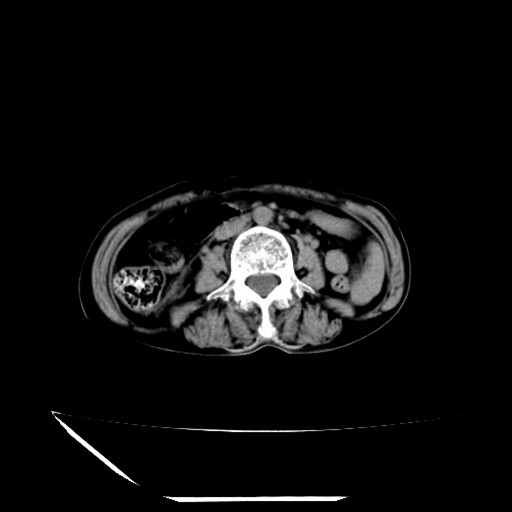

标题: CT16840:女-63岁,下腹部疼痛,

补充资料:血象是13.5,临床拟诊阑尾炎

本人诊断是右肾周围炎,阑尾炎,盆腔少许积液!

诊断右肾周围炎是因为我图像没有发完,诊断阑尾炎是因为相当于阑尾区连续两个层面可以看到增粗的阑尾显影。

支持阑尾炎!局部腹膜增厚,脂肪密度增高。应该手术治疗。